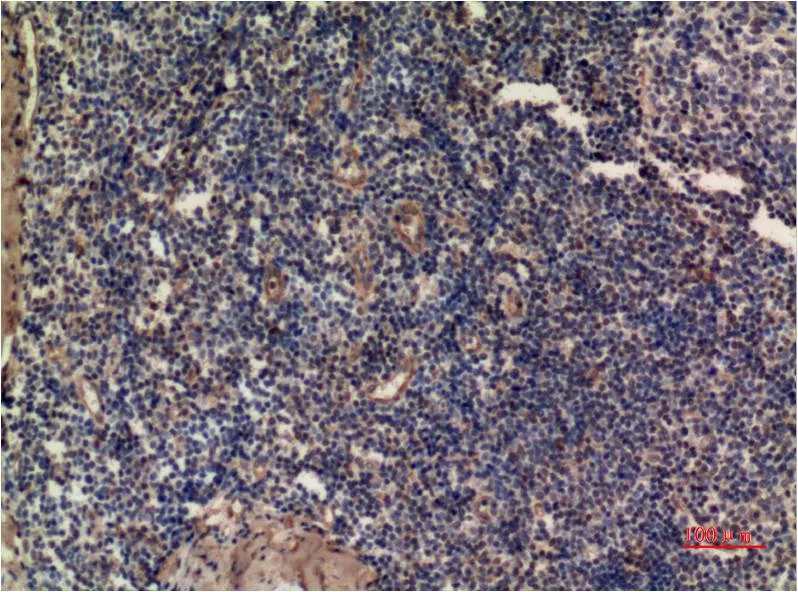

IL-8 (3A4) Mouse Monoclonal Antibody

Cat: AMM00739

Application:IHC-P

Reactivity:Human,Rat,Mouse

Conjugate:Unconjugated

Gene Name:CXCL8